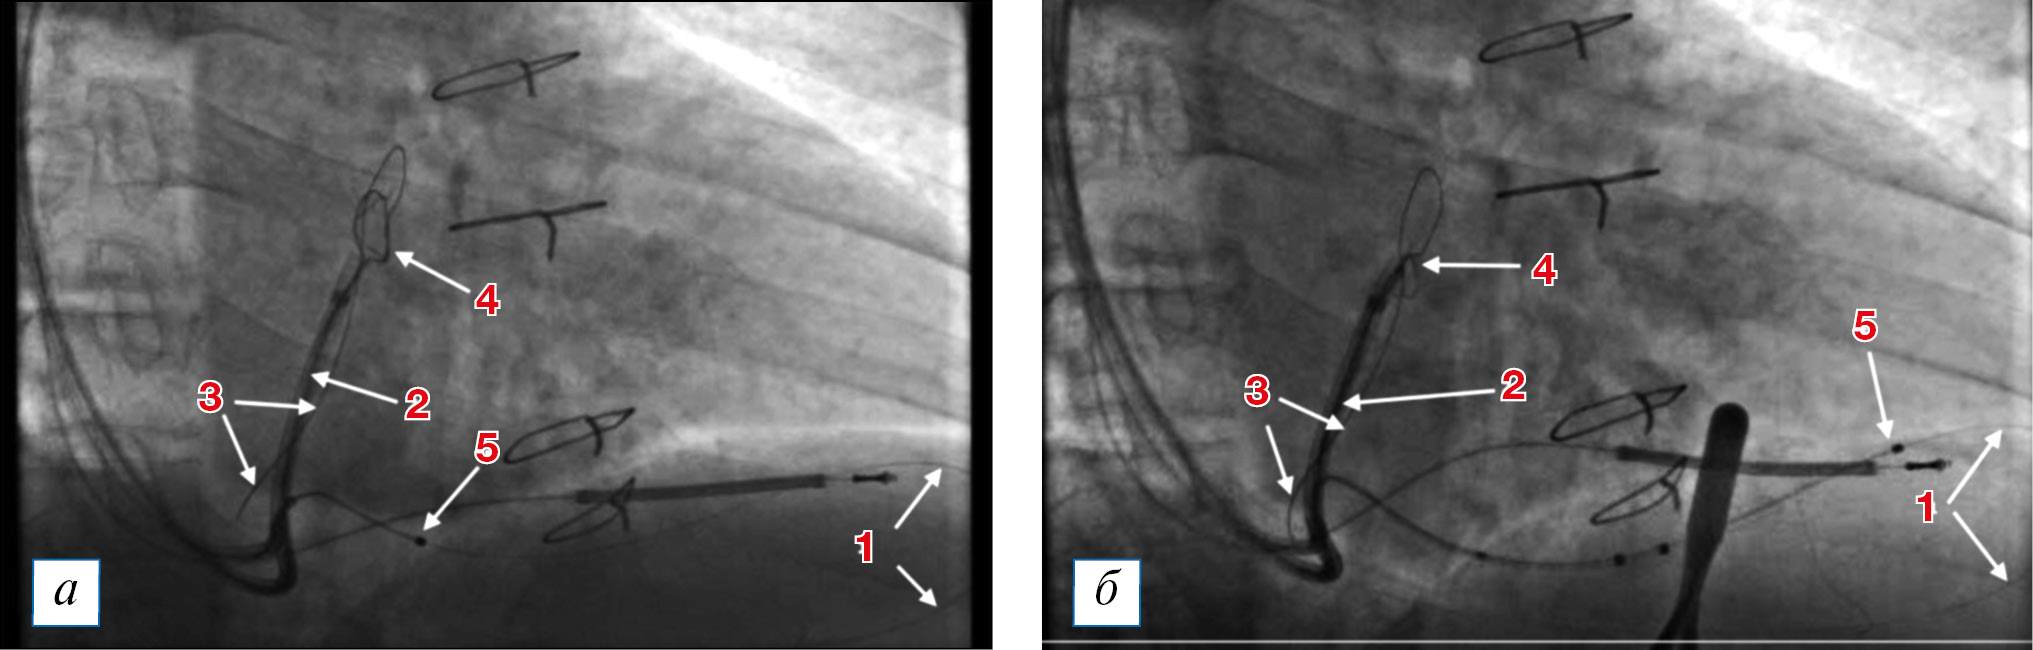

Было принято решение использовать ортодромный ловушечный метод позиционирования левожелудочкового электрода с целью преодоления имеющихся анатомических трудностей. В большую вену сердца была введена вторая система доставки, по которой проведена ловушка типа Goose Neck (гусиная шея) для захвата дистального конца коронарного проводника в большой вене сердца с целью формирования замкнутой петли (рис. 3, а). После создания петли из коронарного проводника электрод удалось завести и позиционировать в нужную зону (рис. 3, б), при этом стимуляционный полюс был расположен вблизи целевой зоны, что видно на правой и левой косой проекциях при рентгеноскопии (рис. 3, б; 4). Параметры порога стимуляции с дистального полюса левожелудочкового электрода в данной области — 2,0 В при 0,4 мс, сенсинг (порог чувствительности) — 11 мВ, импеданс — 750 Ом. Параметры порога стимуляции с полюса ring 2 (второй кольцевой полюс) левожелудочкового электрода (расценен как наиболее предпочтительный для стимуляции по причине более близкого расположения к целевой зоне стимуляции левого желудочка) — 1,8 В при 0,4 мс, порог чувствительности — 7 мВ, импеданс — 698 Ом.

Рис. 3. Проведение левожелудочкового электрода в заднелатерельную вену сердца (правая косая проекция, 30°): 1 — коронарный проводник, проведенный в заднелатеральную вену сердца и через коллатераль уходящий в среднюю вену сердца; 2 — вторая система доставки, через которую проведена ловушка типа Goos Neck (на ее рентгенологическую тень накладывается восходящая часть коронарного проводника в большой вене сердца, который выходит из устья средней вены сердца); 3 — самая дистальная часть коронарного проводника, загибающегося в верхней части большой вены сердца и спускающегося обратно к устью коронарного синуса (на панели 3б — захвачен ловушкой в верхней части); 4 — ловушка типа Goos Neck, проведенная по второй системе доставки (на панели 3а — в распущенном состоянии, на панели 3б — захватывающая коронарный проводник в большой вене сердца, формируя замкнутую петлю коронарного проводника, идущего через заднелатеральную вену сердца, коллатераль, среднюю вену сердца); 5 — дистальный конец левожелудочкового электрода (на панели 3а — в проксимальной части заднелатеральной вены, на панели 3б — в дистальной части заднелатеральной вены в области латеральной стенки левого желудочка). / Fig. 3. Passage of the left ventricular lead into the posterolateral cardiac vein (right anterior oblique projection, 30°): 1 — coronary guidewire is in the posterolateral cardiac vein and is going through the collateral to the middle cardiac vein; 2 — the second left ventricular lead delivery system was positioned in the great cardiac vein. Within the second delivery system, the goose neck snare was introduced. The X-ray shadow of the snare overlaps with the shadow of the ascending part of the guidewire in the great cardiac vein; 3 — the most distal part of the guidewire folded in the upper part of the great cardiac vein and descending back to the coronary sinus ostium (in the 3-rd panel, the capture of the guidewire by the snare is shown); 4 — the goose neck snare is in the second lead delivery system (in panel 3а, the snare is relaxed, in panel 3б, the snare is tightened, the guidewire was captured with the formation of a closed loop, going through the posterolateral cardiac vein, collateral vein and middle cardiac vein); 5 — the distal tip of the left ventricular lead (in panel 3а — the lead tip is in the proximal part of the posterolateral vein, in panel 3б — the lead tip is in the distal part of the posterolateral vein).